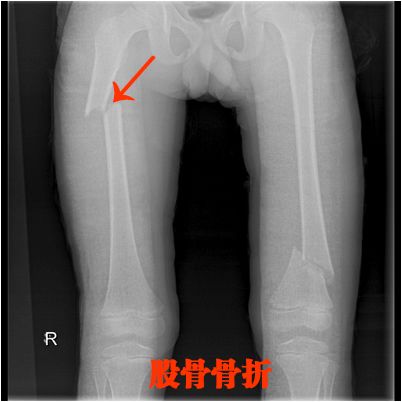

四、长骨骨折

就是四肢的长骨骨折

上肢:

肱骨、尺骨、桡骨

下肢:

股骨、股骨头、胫骨、腓骨

骨折非常简单的

这里就不讲解了,大家看片就行

看片